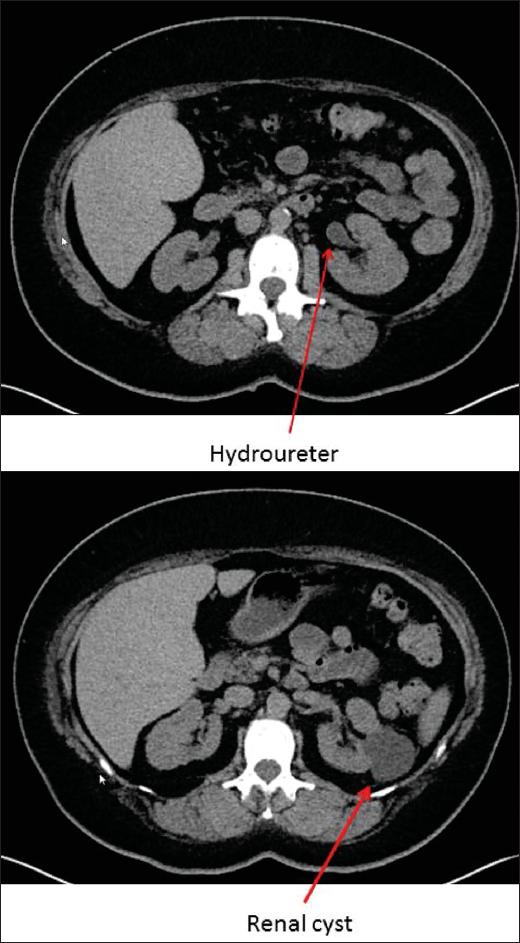

2型强直性肌营养不良症(MD2)是一种多系统疾病,主要影响近端肢体肌肉、眼睛、内分泌器官、心脏和肠道。持续20多年的长期无症状性肌酸激酶升高(高肌酸激酶血症),伴有高脂血症和糖尿病,作为MD2的一种表现尚未见报道。一名52岁女性,自32岁起有高肌酸激酶血症病史,伴有糖尿病、高脂血症和高尿酸血症,51岁时出现心绞痛和近端肌无力,同时握拳时出现临床肌强直。检查发现左前分支阻滞、感觉运动性神经病变、针极肌电图(EMG)显示广泛的肌强直放电,以及基因上134 bp的CCTG扩增。家族史显示有高肌酸激酶血症和肌无力阳性。此外,在过去几年中,她还出现了膀胱输尿管反流、皮肤黑色素瘤、肾囊肿、宫颈发育异常、血小板增多症、白内障、动脉高血压、杂合子因子V莱顿突变、胆囊结石、多个卵巢囊肿和维生素D缺乏。无症状的长期高肌酸激酶血症与多系统疾病相关时应怀疑MD2。MD2的罕见表现可能有血小板增多症、高尿酸血症、膀胱输尿管反流、胆结石、高血压和囊肿形成。对于无症状性高肌酸激酶血症患者,应考虑进行针极EMG检查。如果CCTG扩增较短,2型强直性肌营养不良症可能多年来病情较轻。